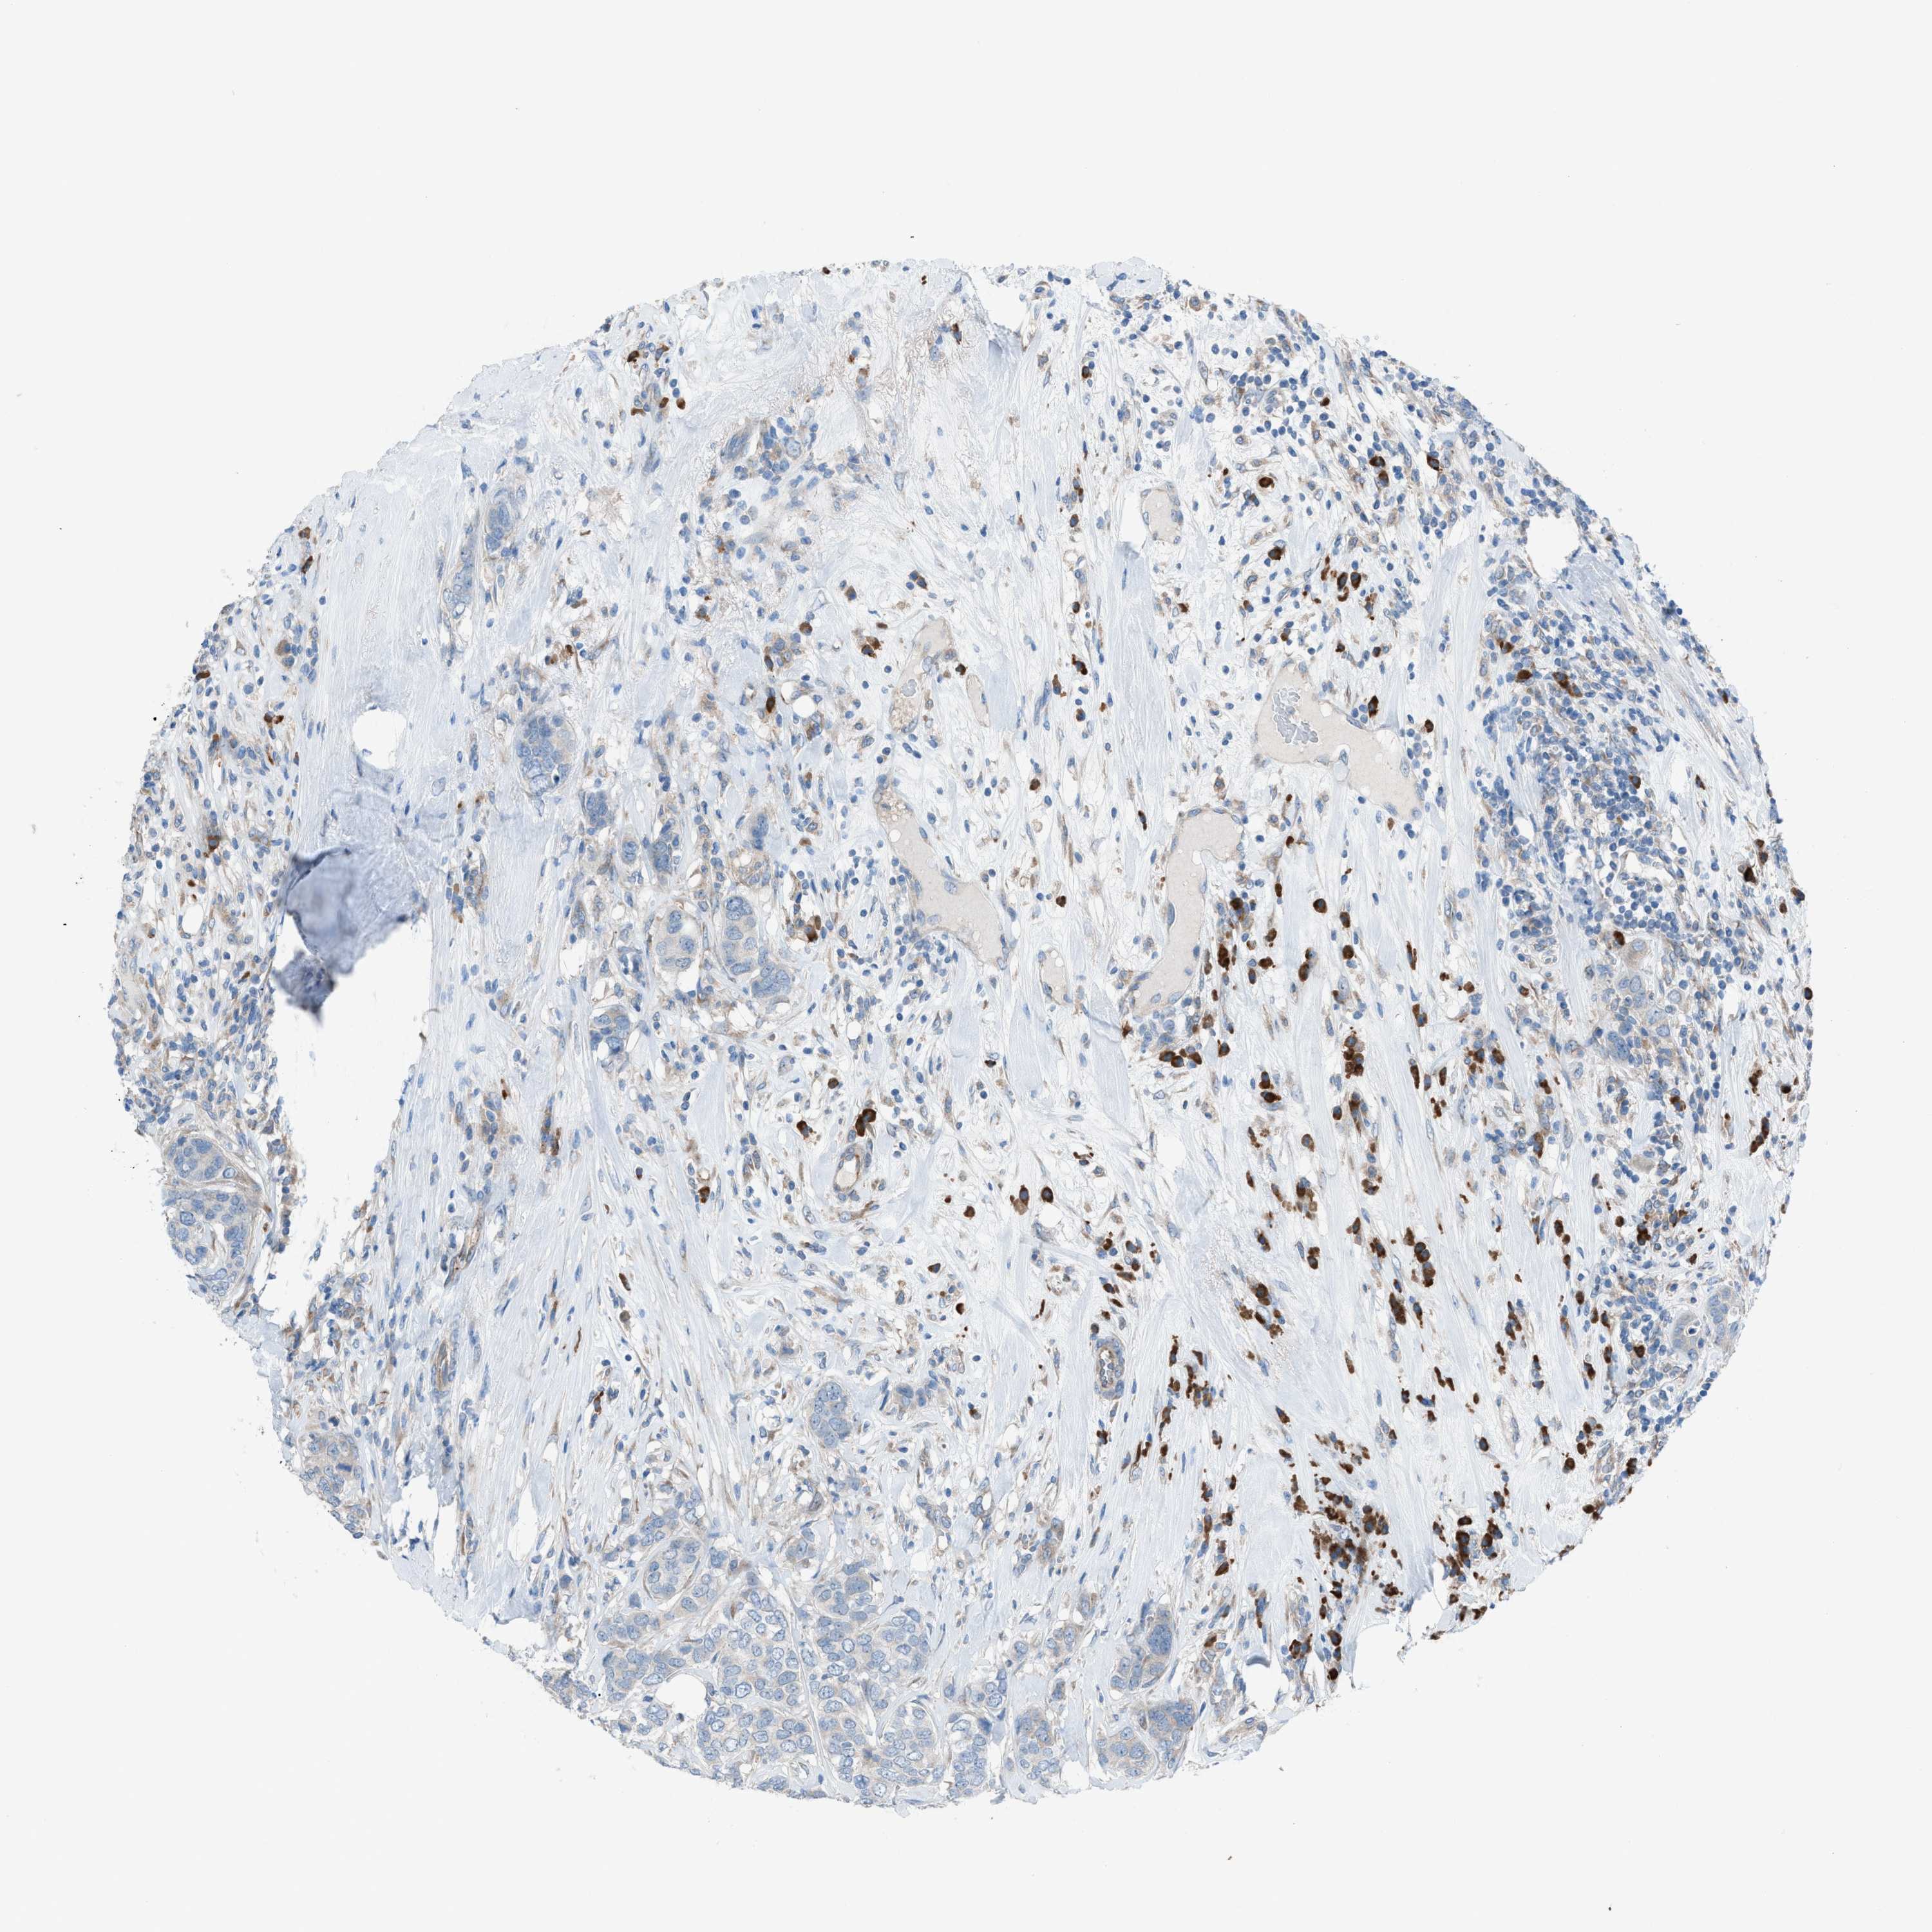

BRCA TCGA BRCA VALIDATION PROTEIN EXPRESSION

ANTIBODIES

AND

VALIDATION